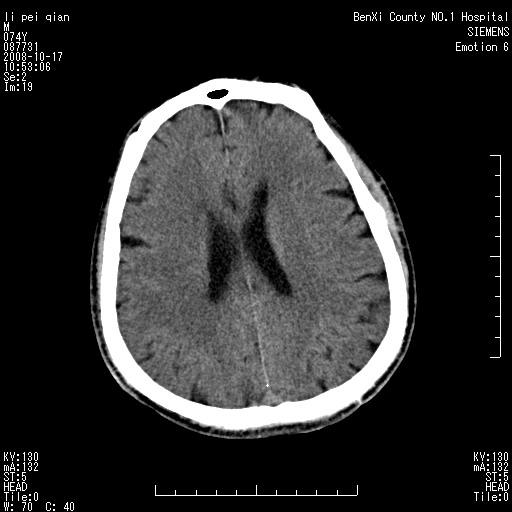

以下是引用影像孺子牛在2008-10-17 11:31:00的发言:[br]考虑:钙化。其一为病变密度特别高,其二如为出血其周围应有水肿带。